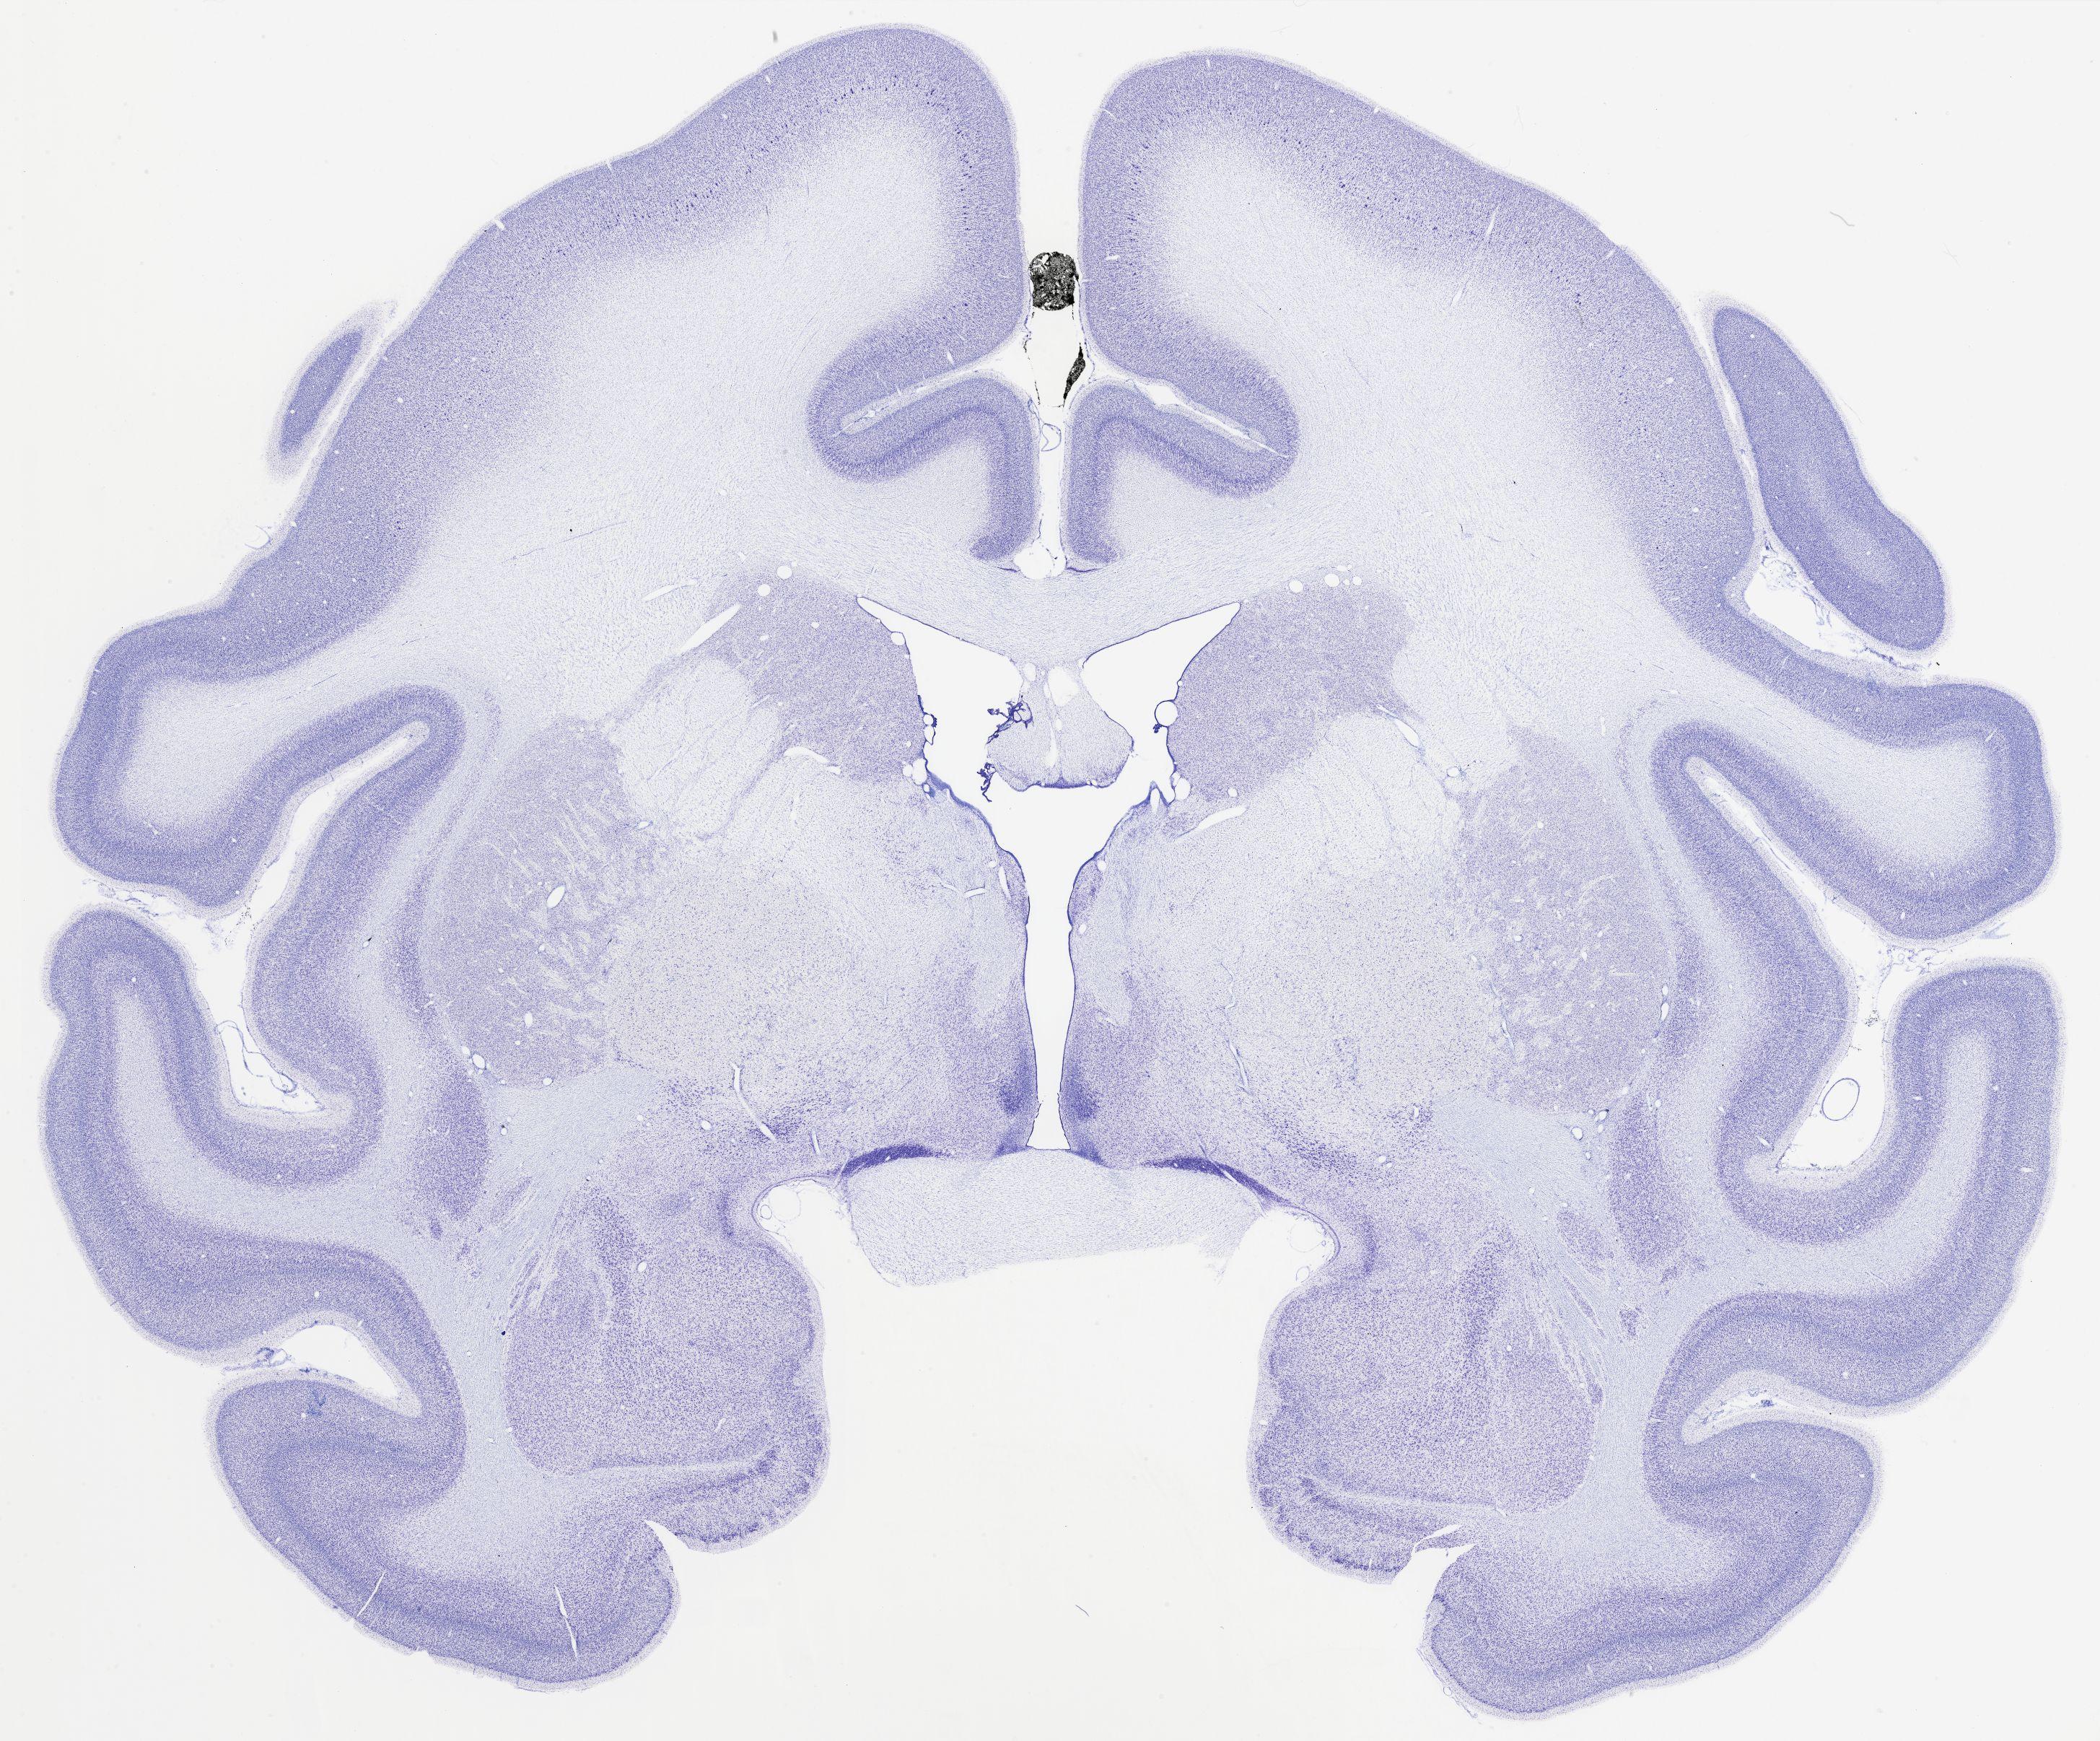

thumbnail

320